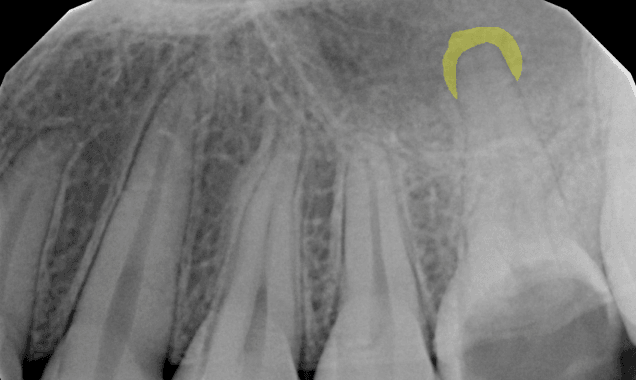

Periapical Radiolucency (PARL)

5/7Our platform is the first FDA-cleared solution that helps dentists detect and segment instances of PARL.